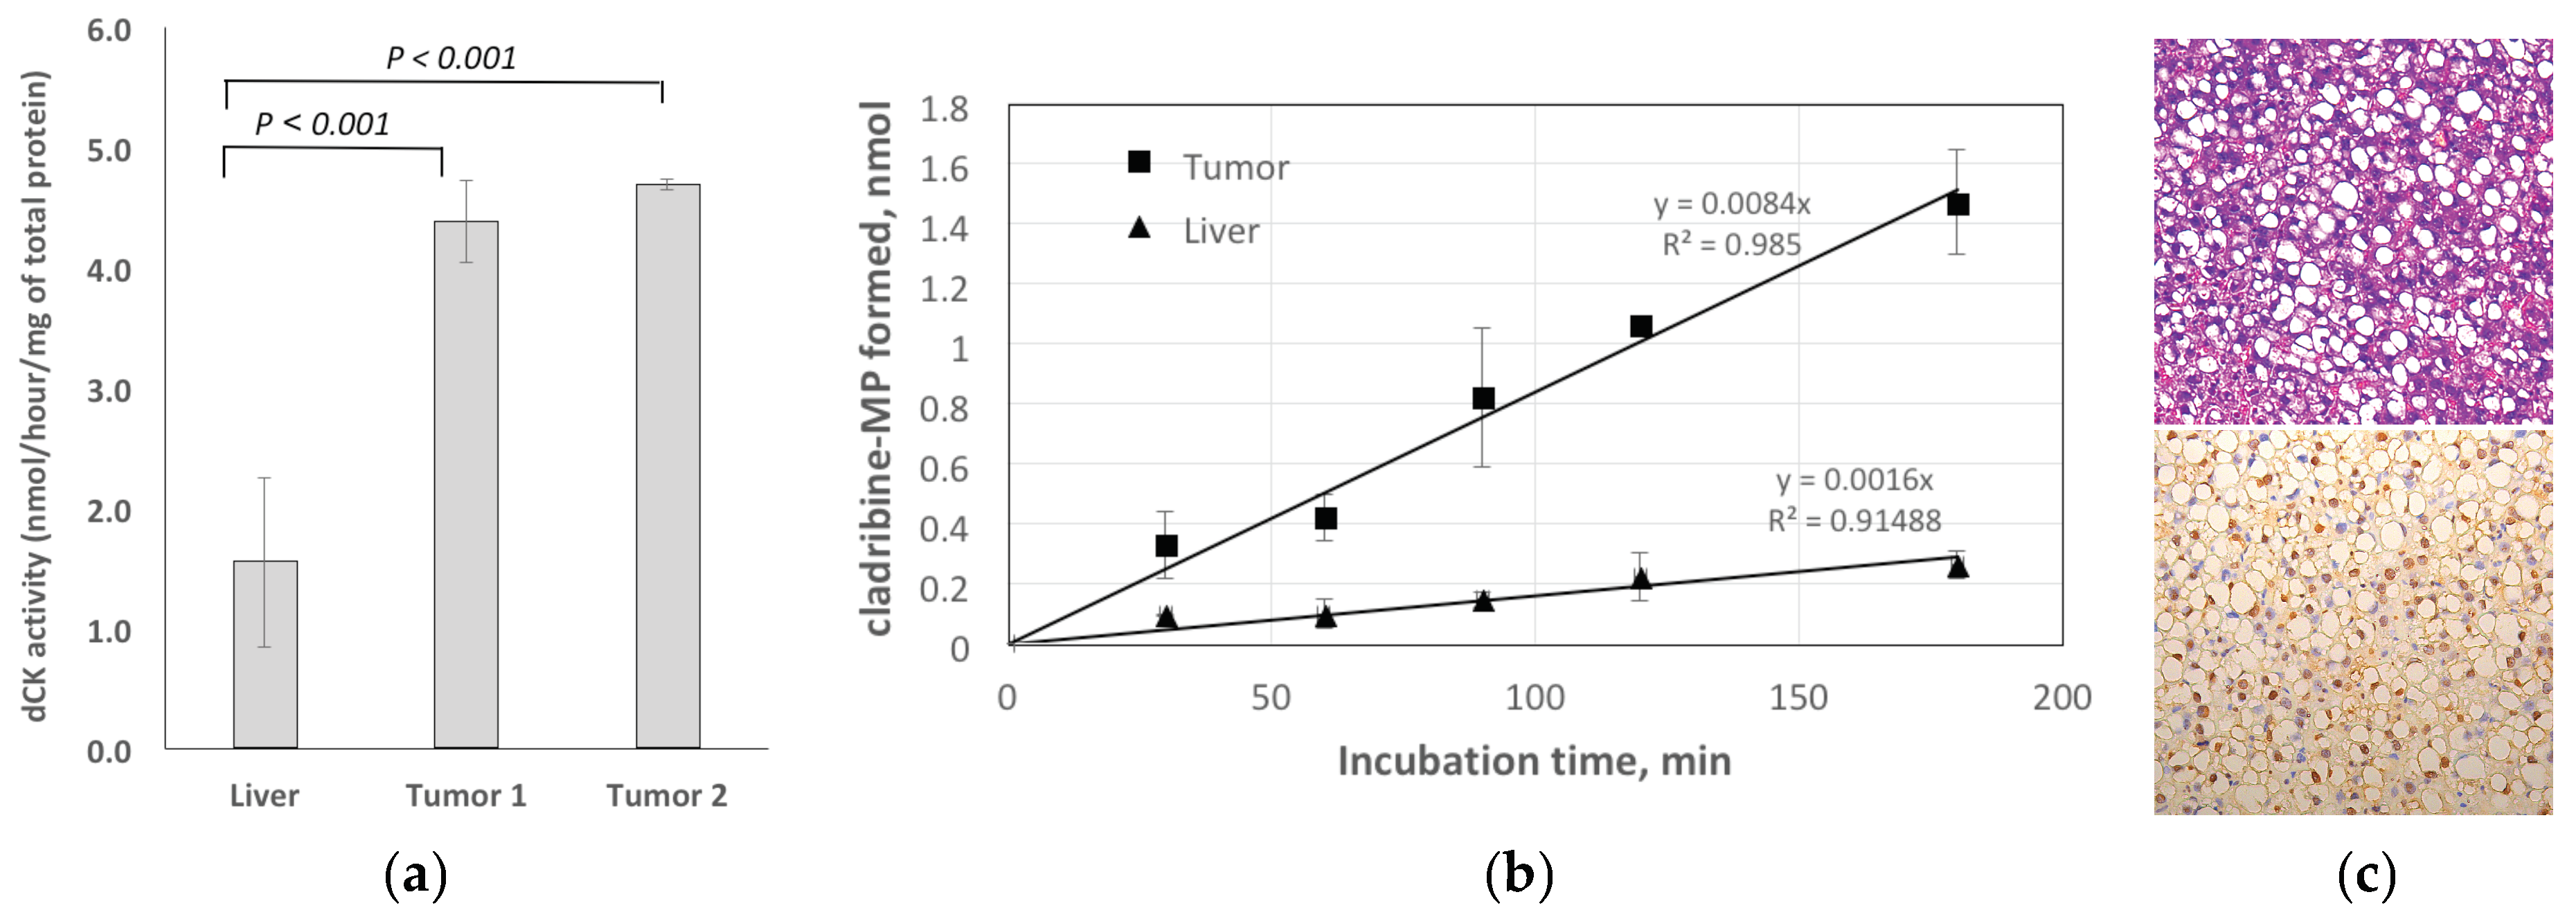

2.3.1. Enzymatic Assay for dCK

2.3.2. Histology

4.4.2. Enzymatic Assay for dCK

4.4.3. Histology